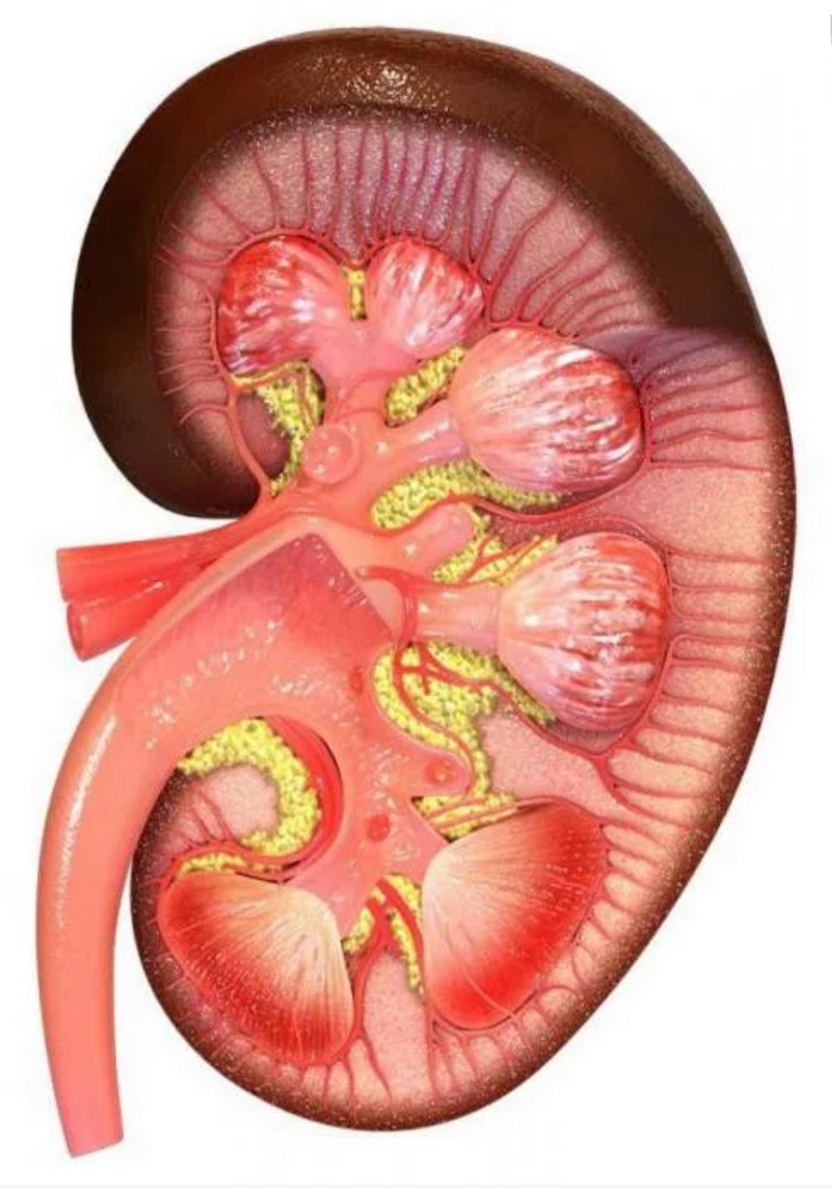

Симптомы подострого гломерулонефрита: фото и описание